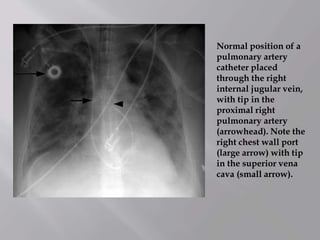

Normal position of a

pulmonary artery

catheter placed

through the right

internal jugular vein,

with tip in the

proximal right

(arrowhead). Note the

right chest wall port

(large arrow) with tip

in the superior vena

cava (small arrow).